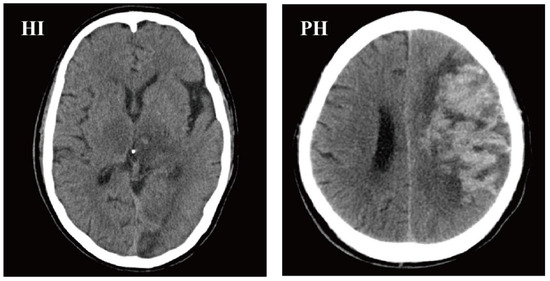

3.2. Characteristics of HI and PH Patients

- Hacke, W.; Kaste, M.; Fieschi, C.; von Kummer, R.; Davalos, A.; Meier, D.; Larrue, V.; Bluhmki, E.; Davis, S.; Donnan, G.; et al. Randomised double-blind placebo-controlled trial of thrombolytic therapy with intravenous alteplase in acute ischaemic stroke (ECASS II). Second European-Australasian Acute Stroke Study Investigators. Lancet 1998, 352, 1245–1251. [Google Scholar] [CrossRef]